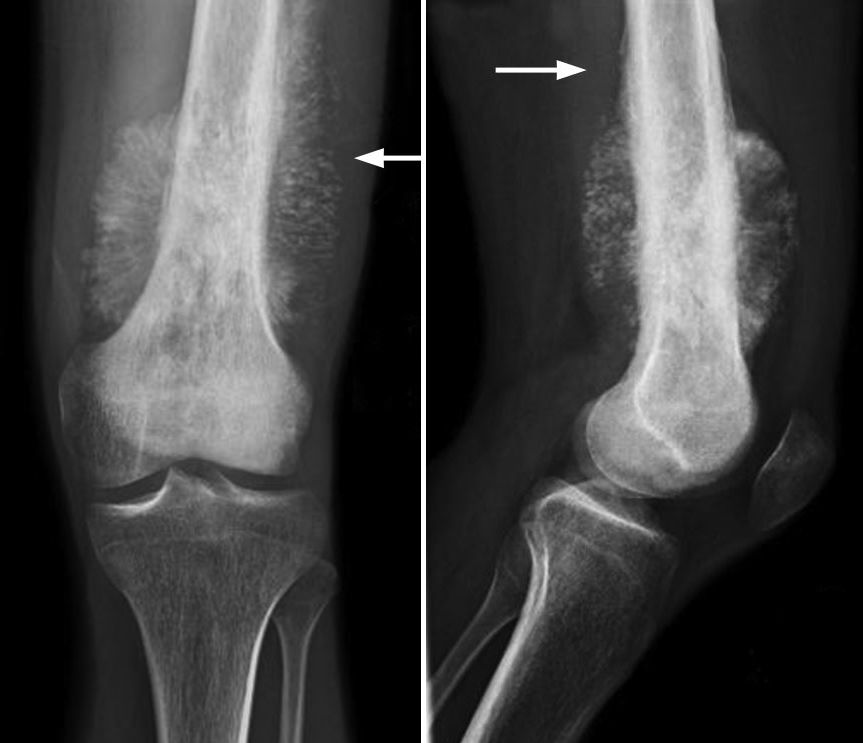

What Are The Symptoms Of Bone Cancer In Leg : Bone Cancer Types Causes Symptoms : Rarely, people with a bone sarcoma may have symptoms such as fever, generally feeling unwell, weight loss, and anemia, which is a low level of red blood cells.. Can bone cancer be found early? These symptoms might indicate that the tibial tumor is metastatic and the primary tumor may be located elsewhere in the body 2. The bone that is removed is replaced with either an implant (prosthesis) or a bone graft, using a healthy part of bone from another part of the body or from a bone bank. If a bone with a tumor breaks, or fractures, in a leg, it can lead to a pronounced limp. Pain in the affected bone is the most common sign of bone cancer.

Each of the four primary forms of bone cancer, osteosarcoma, ewing's sarcoma, chondrosarcoma and spindle cell, have been known to metastasize in the femur. Below are some of the most common symptoms of bone cancer that pet parents should watch for: This spread is called metastasis. Although breast cancer can spread to any bone, the most common sites are the ribs, spine, pelvis, and long bones in the arms and legs. As the cancer grows, the pain will be there all the time, and get worse with activity. When cancer spreads to the bones. Whether primary or metastatic, cancer in the bones may present with symptoms such as increasing pain, swelling and/or a more sudden intense pain from a pathologic fracture —a fracture that occurs in a bone that has been weakened by the presence of tumor. Lumps, swellings, fractures, joint tenderness and pain are some common symptoms of bone cancer in ankle and foot. In general, bone cancer in cats is a rare cancer. The affected leg or joint develops pain that is often described as consistent and dull, like a persistent ache. Bone pain is the most common symptom of metastatic bone cancer. Rarely, people with a bone sarcoma may have symptoms such as fever, generally feeling unwell, weight loss, and anemia, which is a low level of red blood cells. Osteosarcoma is a type of bone cancer that begins in the cells that form bones.

Bone Tumors Varicose Veins Vascular Surgeon Stroke Dvt Leg Gangrene Cancer from virclinic.com Symptoms of bone cancer in dogs can appear subtly, especially in the early stages of the disease. Can bone cancer be found early? It may be the first sign of metastases. As with any type of cancer, bone cancer of the tibia can cause generalized symptoms 2. Osteosarcoma is a type of bone cancer that begins in the cells that form bones. A tumor may be malignant, which means it's growing aggressively and spreading to other parts of the body. Early bone cancer symptoms include severe localized bone pain, bone pain that is stabbing, throbbing, aching, and excruciating. Signs and symptoms of bone cancer.